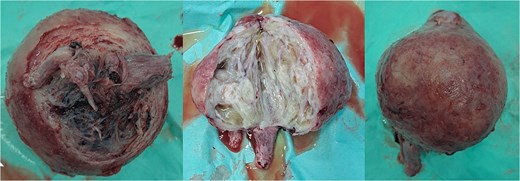

Within the operation, a urinary catheter was inserted and the bladder location was identified. We pushed the mass cranially to reposition the uterus. During repositioning, the cyst mass was ruptured and released serous fluid, exposing the uterine cavity. Another team had started to do a laparotomy and performed a median incision. Intraabdominally, we found a vortex-like structure that had sucked the uterus outside, with a twisted round ligament. We decided to incise the cystic mass to decrease the uterus size, and a sondage was then inserted into the cavity to the cervix inside the abdomen. Then, we made a large bundle of gauze in the sondage handle. We decided to do a double approach to reposition the uterus. The sondage was pulled abdominally and pushed vaginally. Soon, the uterus was reversed, and hysterectomy was performed (Figs 2 and 3). The operation was without complication, with 300 cc of bleeding. Postoperatively, the patient had a good recovery. However, a week after discharge, the wound was not healing properly, with some serous fluid coming out of the wound. A superficial surgical site infection was suspected and managed accordingly, with joint care with internal medicine for her diabetes. The histopathological result was angiomatous leiomyoma submucosum, and no further evaluation was needed.

The uterus with the cervix. The corpus was already dissected and excised from the submucous leiomyoma.